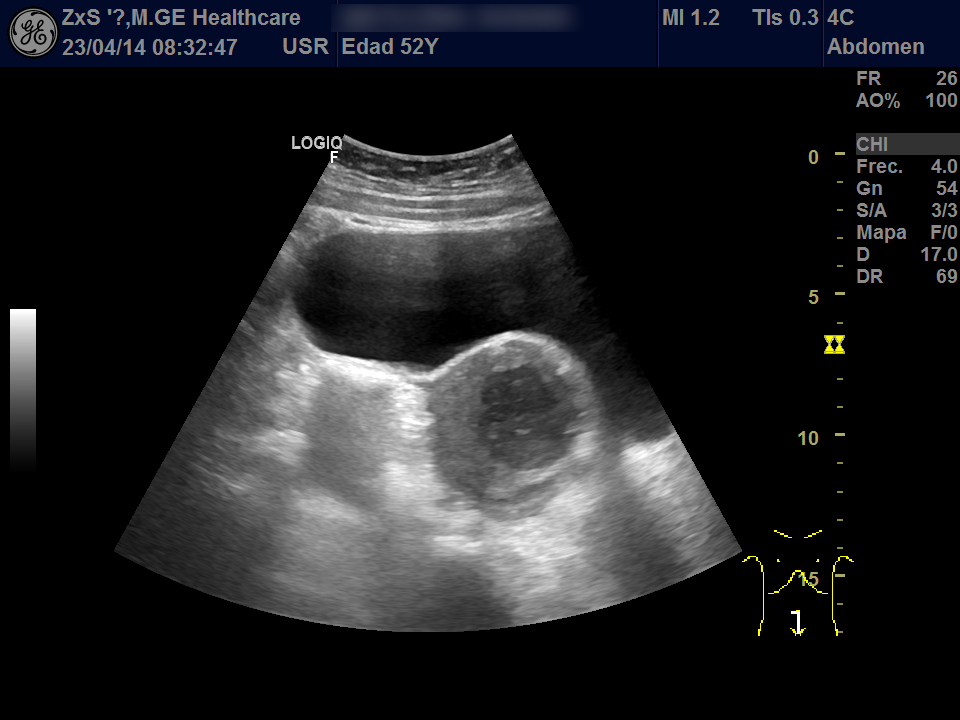

Hígado de bordes lisos y ángulo agudo, aspecto heterogéneo, no se observan LOES. Vía biliar extra e intrahepática no dilatada. Vesícula poco replecionada sin imágenes en su interior, Murphy ecográfico negativo. Ambos riñones de localización y tamaño normal. Buena diferenciación córtico-sinusal y en riñón derecho discreto aumento del tamaño de la pelvis renal compatible con hidronefrosis grado 2. Vejiga bien replecionada sin ecos en su interior. Se objetiva útero de tamaño normal con una imagen hiperecogénica que corresponde a DIU y en la zona derecha una lesión redondeada de aproximadamente 5,5 x 6,5 de diámetro de contenido heterogéneo que dudamos si puede corresponder a masa ovárica desconocida. Se deriva al hospital por sospecha de masa ovárica.

Evolución y seguimiento: Urgencias hospital TAC abdominal: en región anexial lesión de aspecto sólido-quístico de 6,5 x 5,5 cm con cambios inflamatorios de la grasa adyacente y que produce leve desplazamiento del útero hacia la izda. No se observan colecciones, neumoperitoneo, ni líquido libre intraabdominal.

Dco hospital: Absceso tubo-ovárico Ingreso. Se retira DIU y se pauta tto antibiótico IV. Posterior laparoscopia abierta: Plastrón inflamatorio que alberga trompa y anejo derecha íntimamente adherido a asas intestinales, útero y pared pélvica.